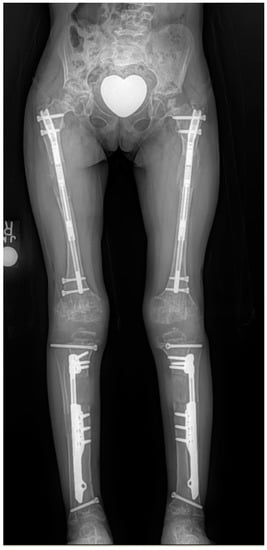

The usual goal in the tibias was 15–16 cm and the goal in the femurs was 10–12 cm. Since 1997, the author switched to simultaneous 4-segment lengthening of both femurs and both tibias at the same time using external fixation [5] (Figure 2, Figure 3, Figure 4, Figure 5, Figure 6 and Figure 7). The femurs were lengthened to a maximum goal of 8 cm and the tibias to 7 cm, for a total gain in height of 15 cm. This method was later modified to do bilateral femoral lengthening with implantable lengthening nails simultaneous with bilateral tibial lengthening with external fixation (Figure 8 left). This was referred to as 4-segment hybrid lengthening (Figure 8 middle). Since 2014, with the advent of shorter and smaller diameter implantable lengthening nails, 4-segment femur and tibia all implantable nail lengthenings were performed (Figure 8, right) [6,7].

Figure 8.

Radiographs showing 4-segment lengthening with: 4 external fixators (left); Hybrid, 2 implantable lengthening nails in both femurs and two external fixators (middle); and 4 implantable lengthening nails in both femurs and tibias.